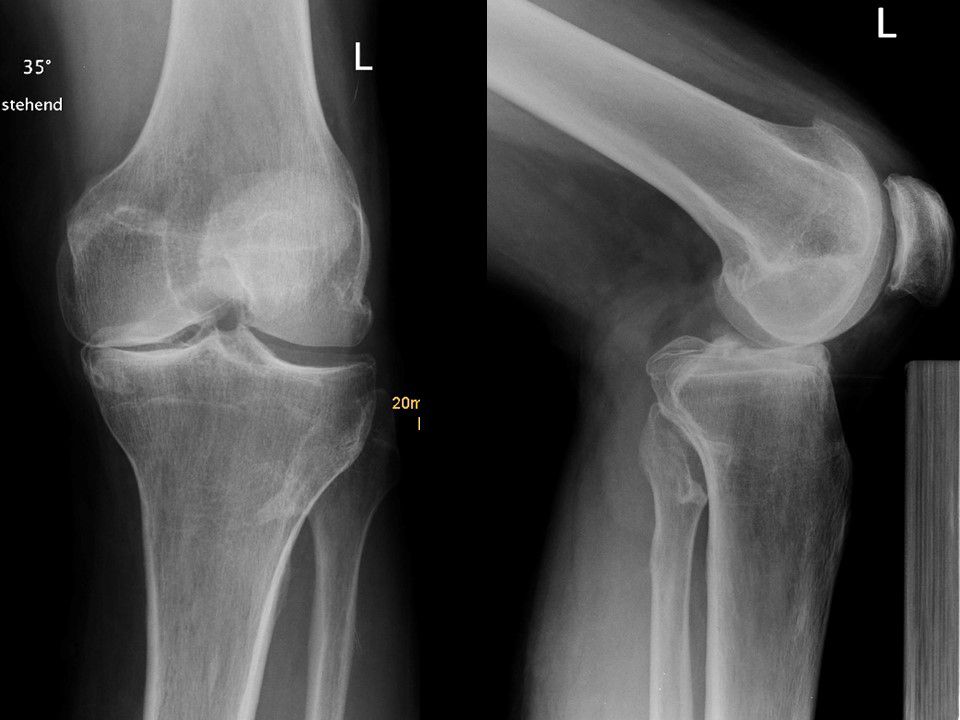

After clinical examination normal x-rays of the knee ap and lateral view is performed. In chronic posterior knee instability, we add standing long film ap x-rays bilateral as well as lateral long film (1/3 Femur and 2/3 Tibia) to detect hyperextension and to measure the slope (Fig 1).

Fig 1 - X- RAY: Long Standing Film  for Alignement Evaluation  and Lateral Hyperextension for Slope Evaluation